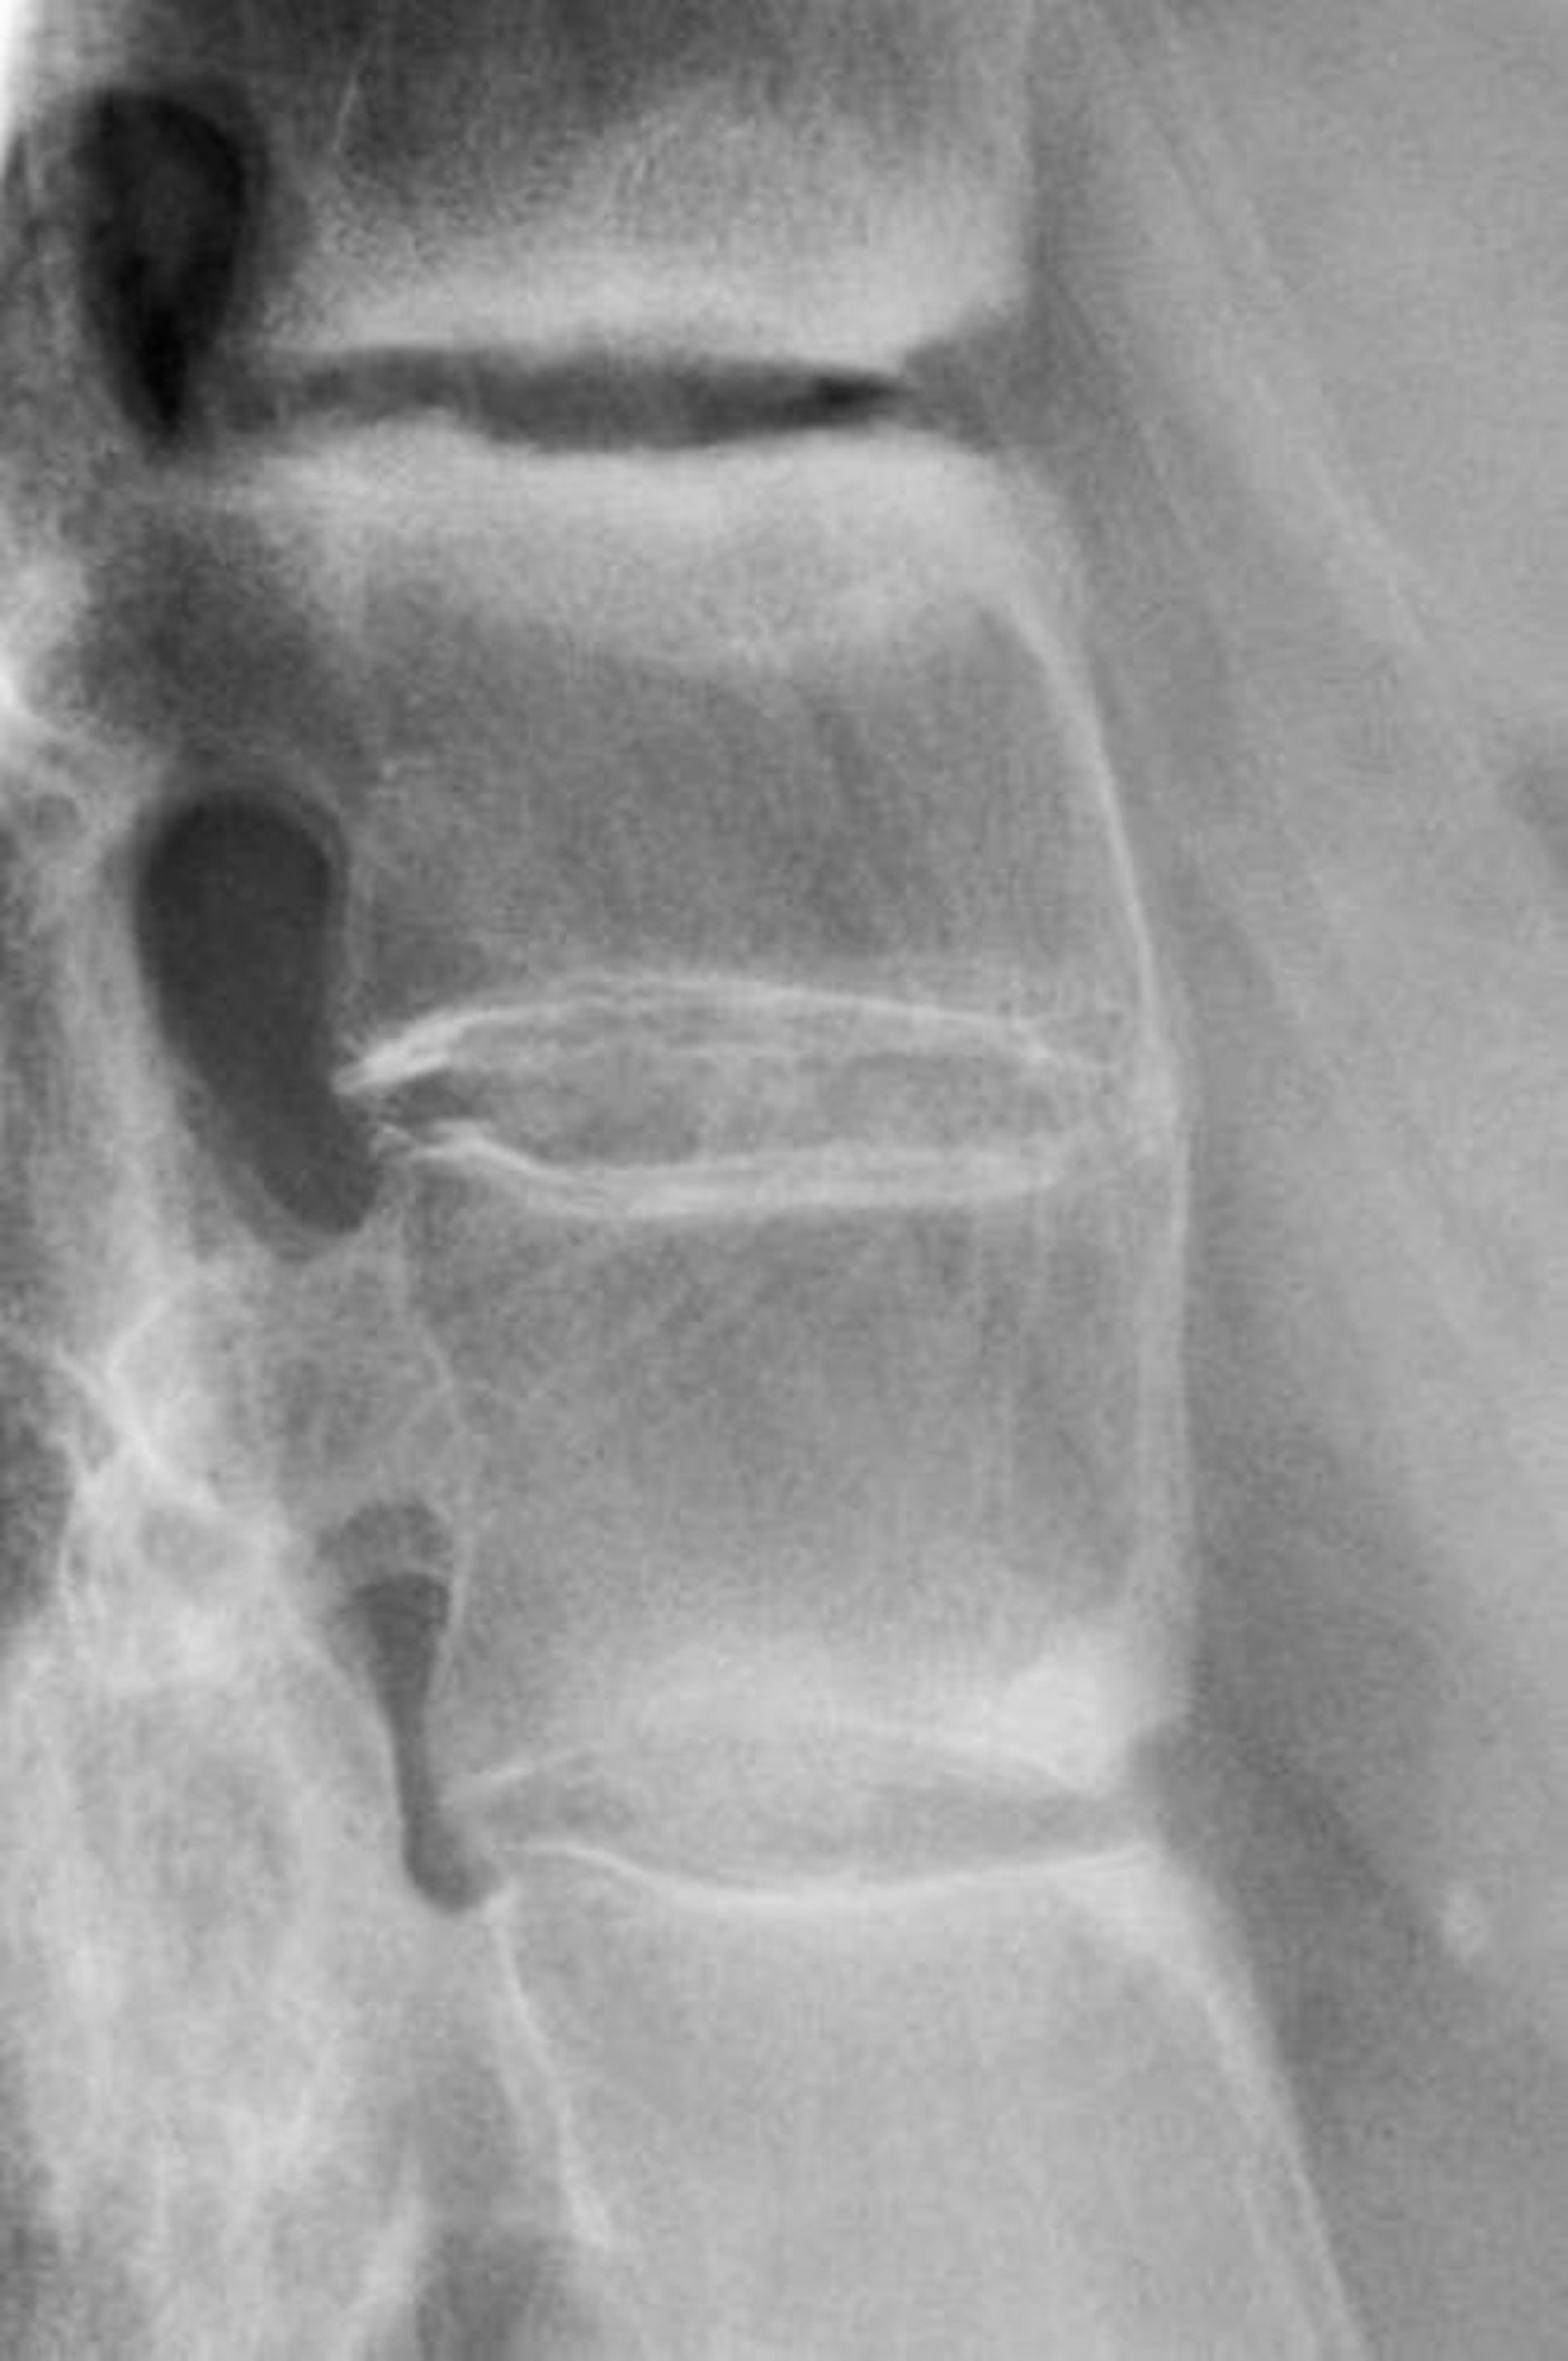

Spondilite anchilosante

Questa radiografia mostra sclerosi tra le vertebre lombari, perdita della lordosi, e fusione delle vertebre lombari, un reperto che indica una forma avanzata di spondilite anchilosante.

DR P. MARAZZI/SCIENCE PHOTO LIBRARY